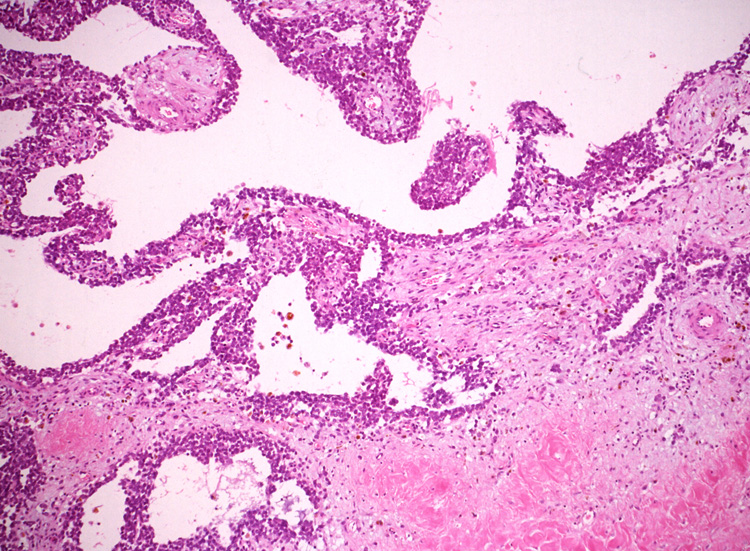

ルーペ像では(Fig.01)ヘモジデリンを貪食したマクロファージに富む線維性間質をもち、腫瘍細胞が胞巣状, 地図状に増殖している。線維性間質はdesmoplasticではなく成熟した線維組織のようである。本例ではさらに腫瘍胞巣内にタンパク液の貯留した偽嚢胞様構造が散在するほか、層状の腫瘍細胞に裏装された嚢胞様構造が出現している。(Fig.03,04)